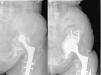

Paciente de 49 años con PTC implantada en otro centro 20 años antes, tras un accidente. A) Radiografía anteroposterior donde se observa movilización del componente acetabular con evidencia de discontinuidad pélvica debido a una seudoartrosis. B) Radiografía anteroposterior postoperatoria inmediata. C) Control radiográfico a los 6 meses, con descementación del polietileno. D) Control radiográfico en el postoperatorio inmediato tras el recambio de polietileno.